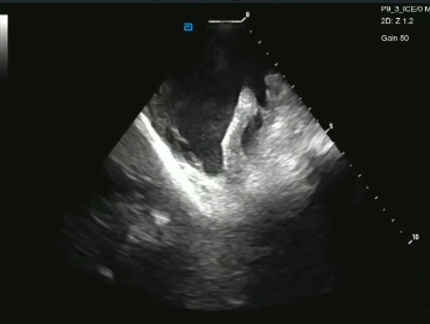

Use the ViewMate™ Multi Ultrasound System with ViewFlex™ Xtra ICE Catheter to visualize cardiac structures, blood flow and devices within the heart.

The ViewMate Multi Ultrasound System delivers superb image quality across the entire field and intuitive touch-screen capabilities, all on a robust platform built for 4D ICE capabilities.

The ViewFlex™ Xtra ICE Catheter provides seamless maneuverability, allowing physicians to focus more on the procedure and less on catheter manipulation to enhance workflow efficiency.